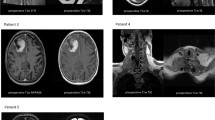

To investigate the relationship between gene expressions and CNV/MET, 604 DEGs were used for prognostic survival analysis. Univariate survival analysis determined 127 genes significantly associated with sarcoma prognosis, among them 41 gene were closely associated with PFS in at least two data sets (Additional file 3: Figure S3B). Three of the most significant genes, namely, ENO1, ACVRL1 and APBB1IP, were further used to analyze the relationship of their expressions and CNV and methylation. It has been found that the expression of ENO1 gene was positively correlated with CNV (Fig. 7a), noticeably, ENO1 expressed significantly higher in the iC2 subtype with the worst prognosis than in other subtypes (Fig. 7b). Correspondingly, high-expressed ENO1 was associated with worse prognosis recorded in TCGA and GSE21050 (Fig. 7c, d). The expressions of ACVRL1 and APBB1IP were negatively correlated with methylation (Fig. 7e–i), moreover, the two genes exhibited high expressions in the iC4 subtype with the most optimal prognosis (Fig. 7f–j), and their high expressions were related to a better prognosis (Fig. 7g, h, k, l). RT-qPCR assay results indicated that ENO1 was upregulated, whereas ACVRL1 and APBB1IP were downregulated in Hs 729 sarcoma cells that in 10.014 pRSV-T cells (Additional file 4: Figure S4).

a–d Correlation between NO1 gene methylation and expression, expression of NO1 in iC subtype, OS KM curve of samples from high-expression group and low-expression group in TCGA data, and OS KM curve of samples from high-expression group and low-expression group of GSE21050 verification set. e–h Correlation between ACVRL1 gene methylation and expression, expression of ACVRL1 in iC subtype, OS KM curve of samples from high-expression group and low-expression group of GSE21050 data and GSE7118 data. i–l Correlation between APBB1IP gene methylation and expression, expression of APBB1IP in iC subtype, OS KM curve of samples from high-expression group and low-expression group of GSE21050 data and GSE7118 data